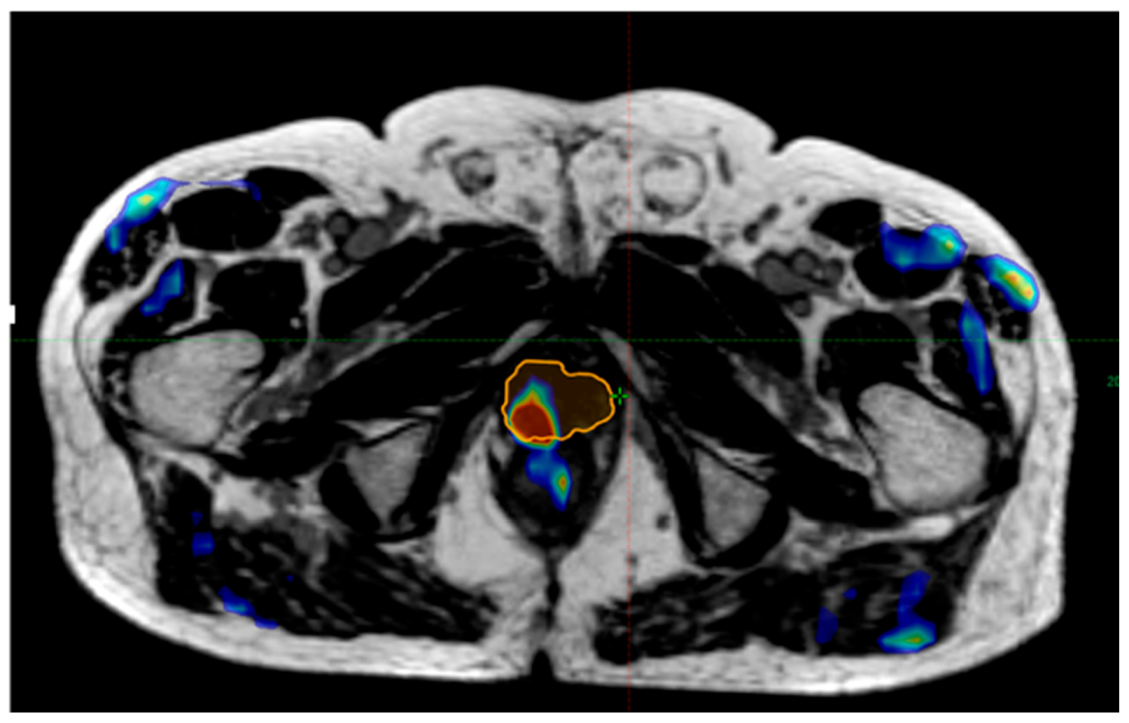

Topography of Recurrences